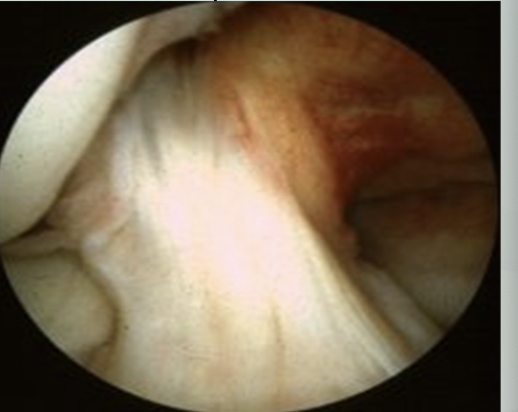

How fast is the person likely moving here?

Jogging